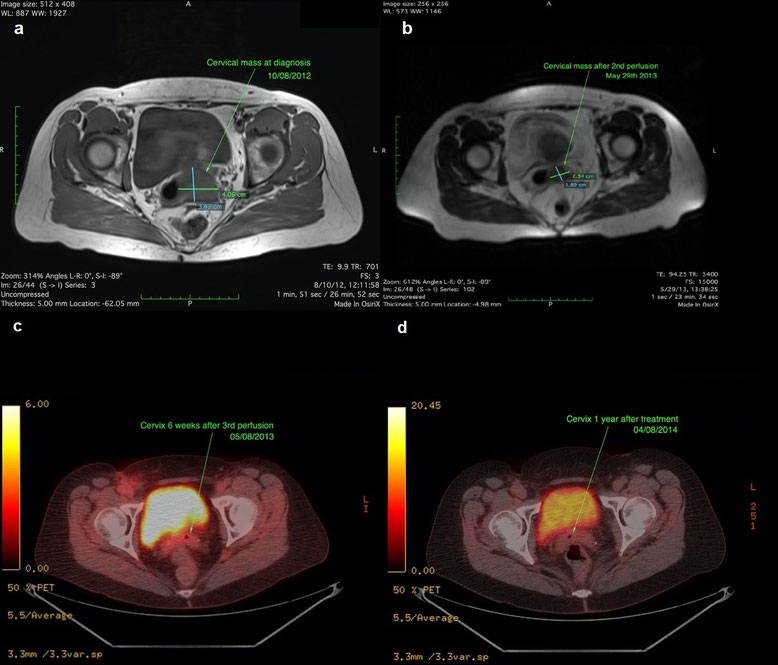

Ein MRT im August 2012 zeigte eine zervikale Raumforderung von 3,43 x 4,06 cm. Eine CT-Untersuchung des Abdomens und Beckens offenbarte im April 2013 eine zervikale Raumforderung mit einer Größe von 3,86 x 5,83 cm. Es lag kein Hinweis auf eine metastasierende Erkrankung vor. Der behandelnde gynäkologische Onkologe teilte der Patientin mit, dass sie an einer inoperablen Erkrankung leide. Die Patientin stellte sich kurze Zeit später in unserer Klinik vor.

Nach den ersten zwei HPP-Zyklen mit jeweils 50 mg Cisplatin, 30 mg Adriamycin und 15 mg Mitomycin ergab die gynäkologische Untersuchung einen verkürzten Gebärmutterhals mit Vernarbungen und ohne Anzeichen eines zervikalen oder vaginalen Tumors. Die parametrische Untersuchung erbrachte tastbares Narbengewebe mit verbesserter Mobilität. Die Patientin war schmerzfrei.

Sie erhielt einen zusätzlichen HPP-Zyklus im Juni 2013. Ein MRT des Abdomens und Beckens zeigte im Mai 2013 nach zwei HPP-Zyklen eine zervikale Resttumormasse von 1,89 x 2,34 cm Größe.

Ein im August 2013 durchgeführtes FDG PET-CT zeigte eine unauffällige Zervix ohne metabolische Aktivität. Das im August 2014 zur Nachkontrolle durchgeführte FDG PET-CT zeigte keine Anzeichen eines Rezidivs.

Die Patientin ist seit 7 Jahren tumorfrei.

MRT- und PET-CT-Bildaufnahmen einer Patientin mit fortgeschrittenem Zervixkarzinom vor und nach HPP-Behandlung, zeigend Tumorverkleinerung und vollständige metabolische Remission über ein Jahr.